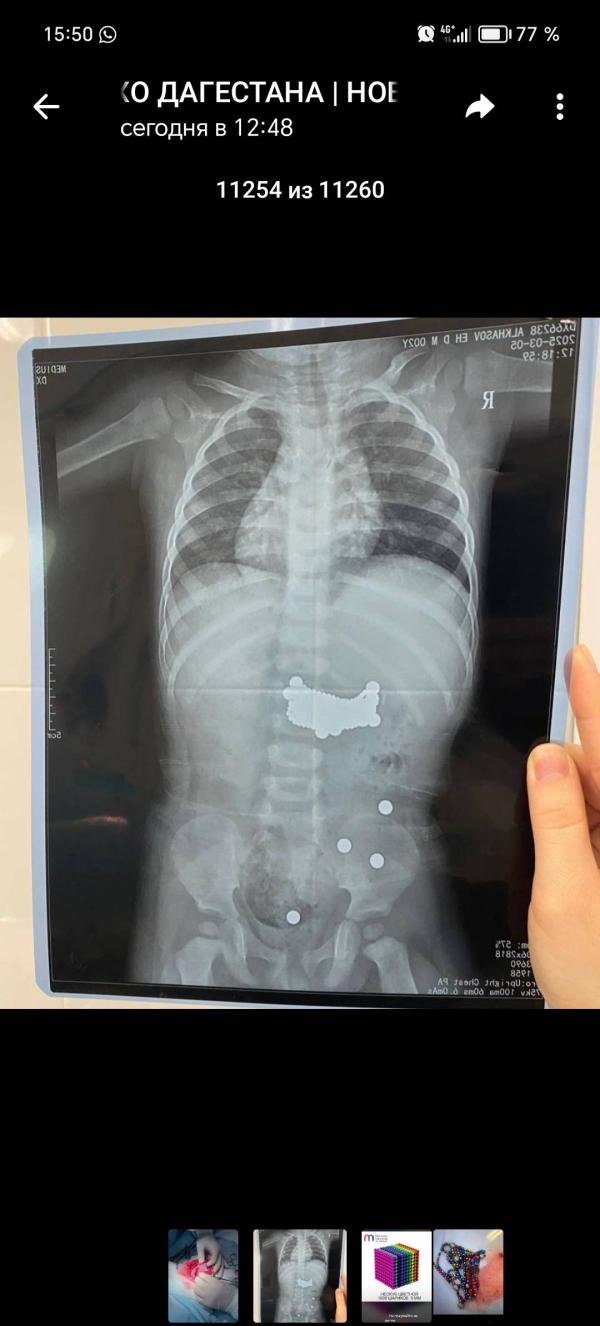

Я в шоке: что произошло?! Невероятная новость, от которой я до сих пор не могу отойти! Обсуждаем

Кошмар(((ужасная игрушка